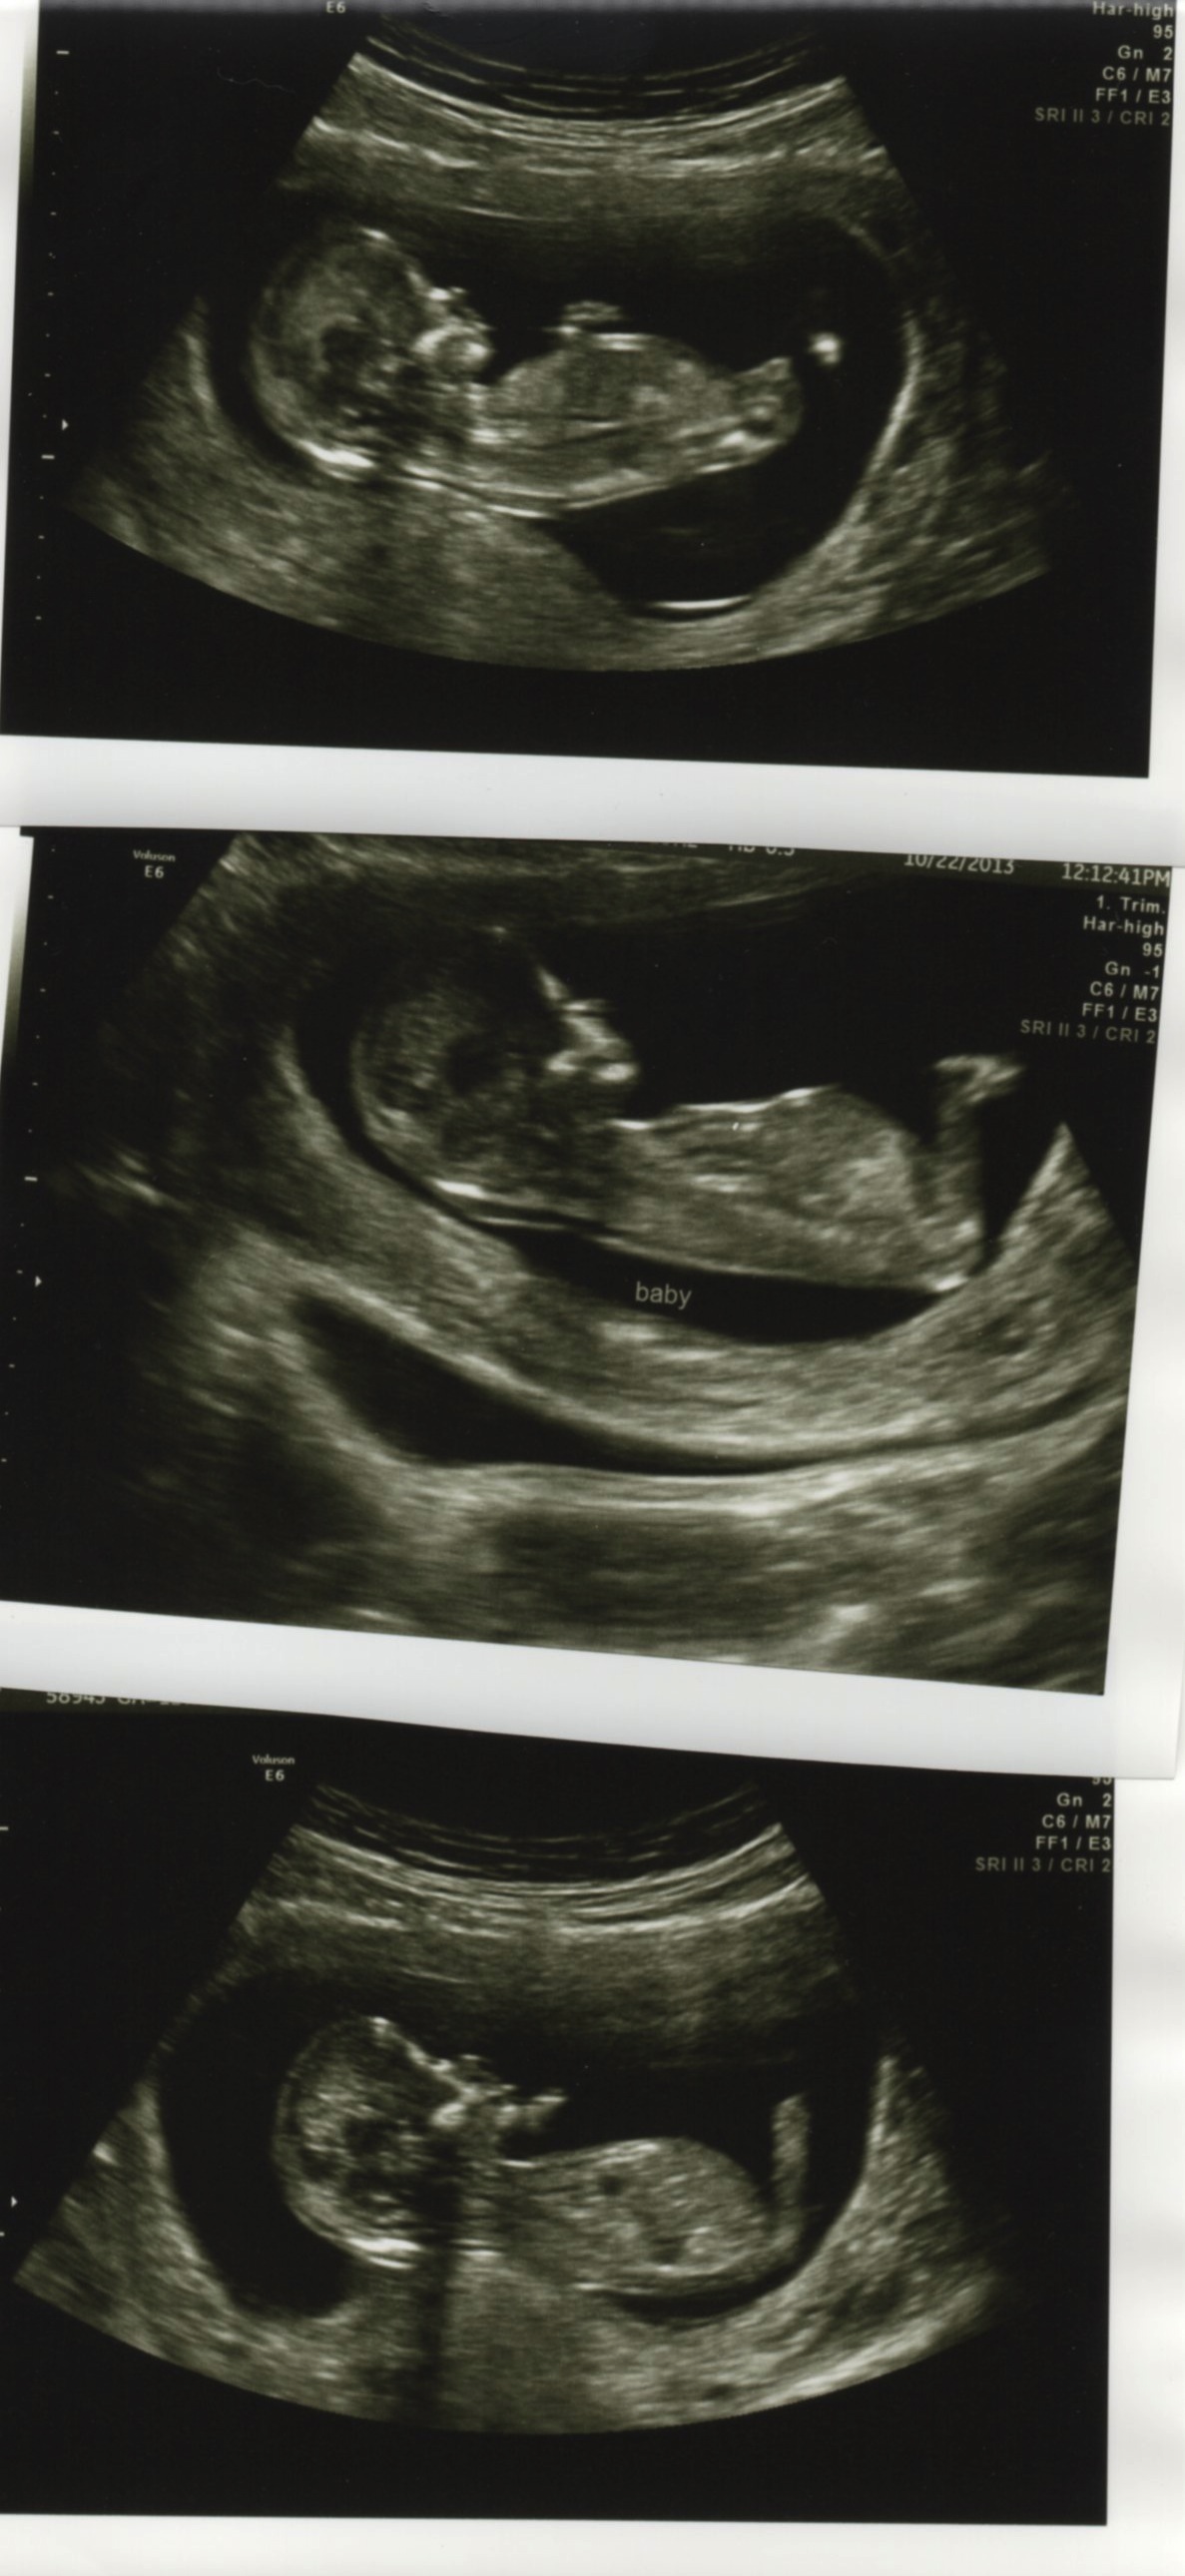

Hopefully these scanned clear enough that you can see. :) I'm new here (and SO happy there are other people who know this theory, my friends think I'm nuts!).

Boy or girl...whatcha think?

1st pic looks girly. 2nd & 3rd are a bit blurry maybe?

Yeah...the second one is blurry compared to viewing it in person. I'm not sure there's a nub there, or not.

Skull is also looking girly :eek:

girl lean. baby's back is stretched flat in the first picture, so it might throw it off a little bit.

Hmmm. I will lean a bit girl. Angle is girly still. But the shape is throwing me off. Could be a fork I am seeing, just not clearly. But could be a bobble, which would lean me boy. Sorry. I'll give a 60-40 girly lean.

Pink